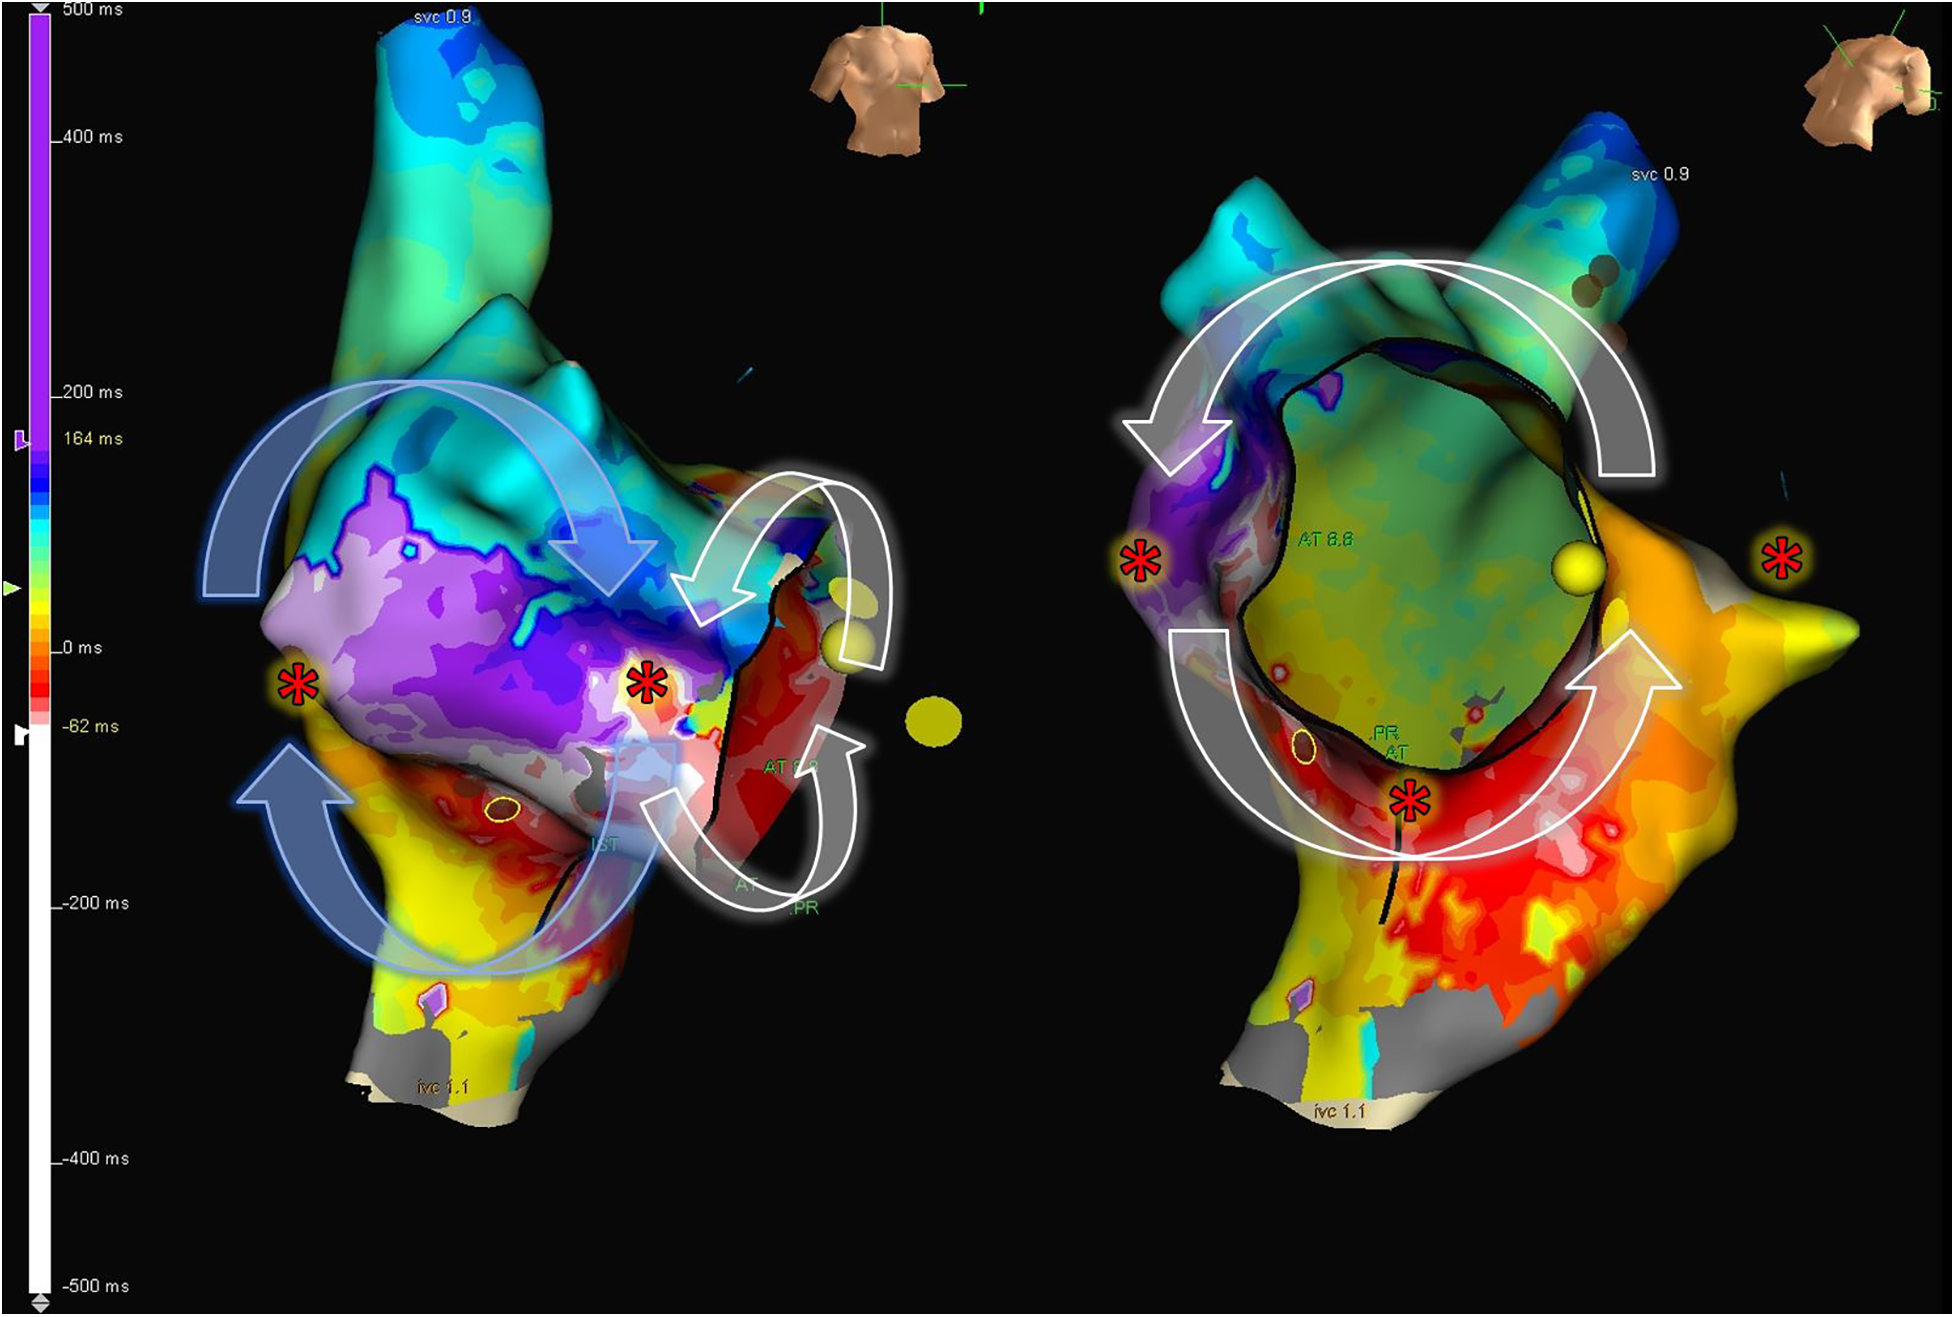

Figure 7

8-shape figure atrial flutter. Electroanatomic map of the right atrium, showing activation during tachycardia in a patient with repaired Tetralogy of Fallot. An 8-shaped figure with counterclockwise rotation around the cavotricuspid isthmus and clockwise rotation in the lateral wall is observed. The “*” indicates sites frequently used to perform entrainment maneuvers to determine the active circuit of the tachycardia.